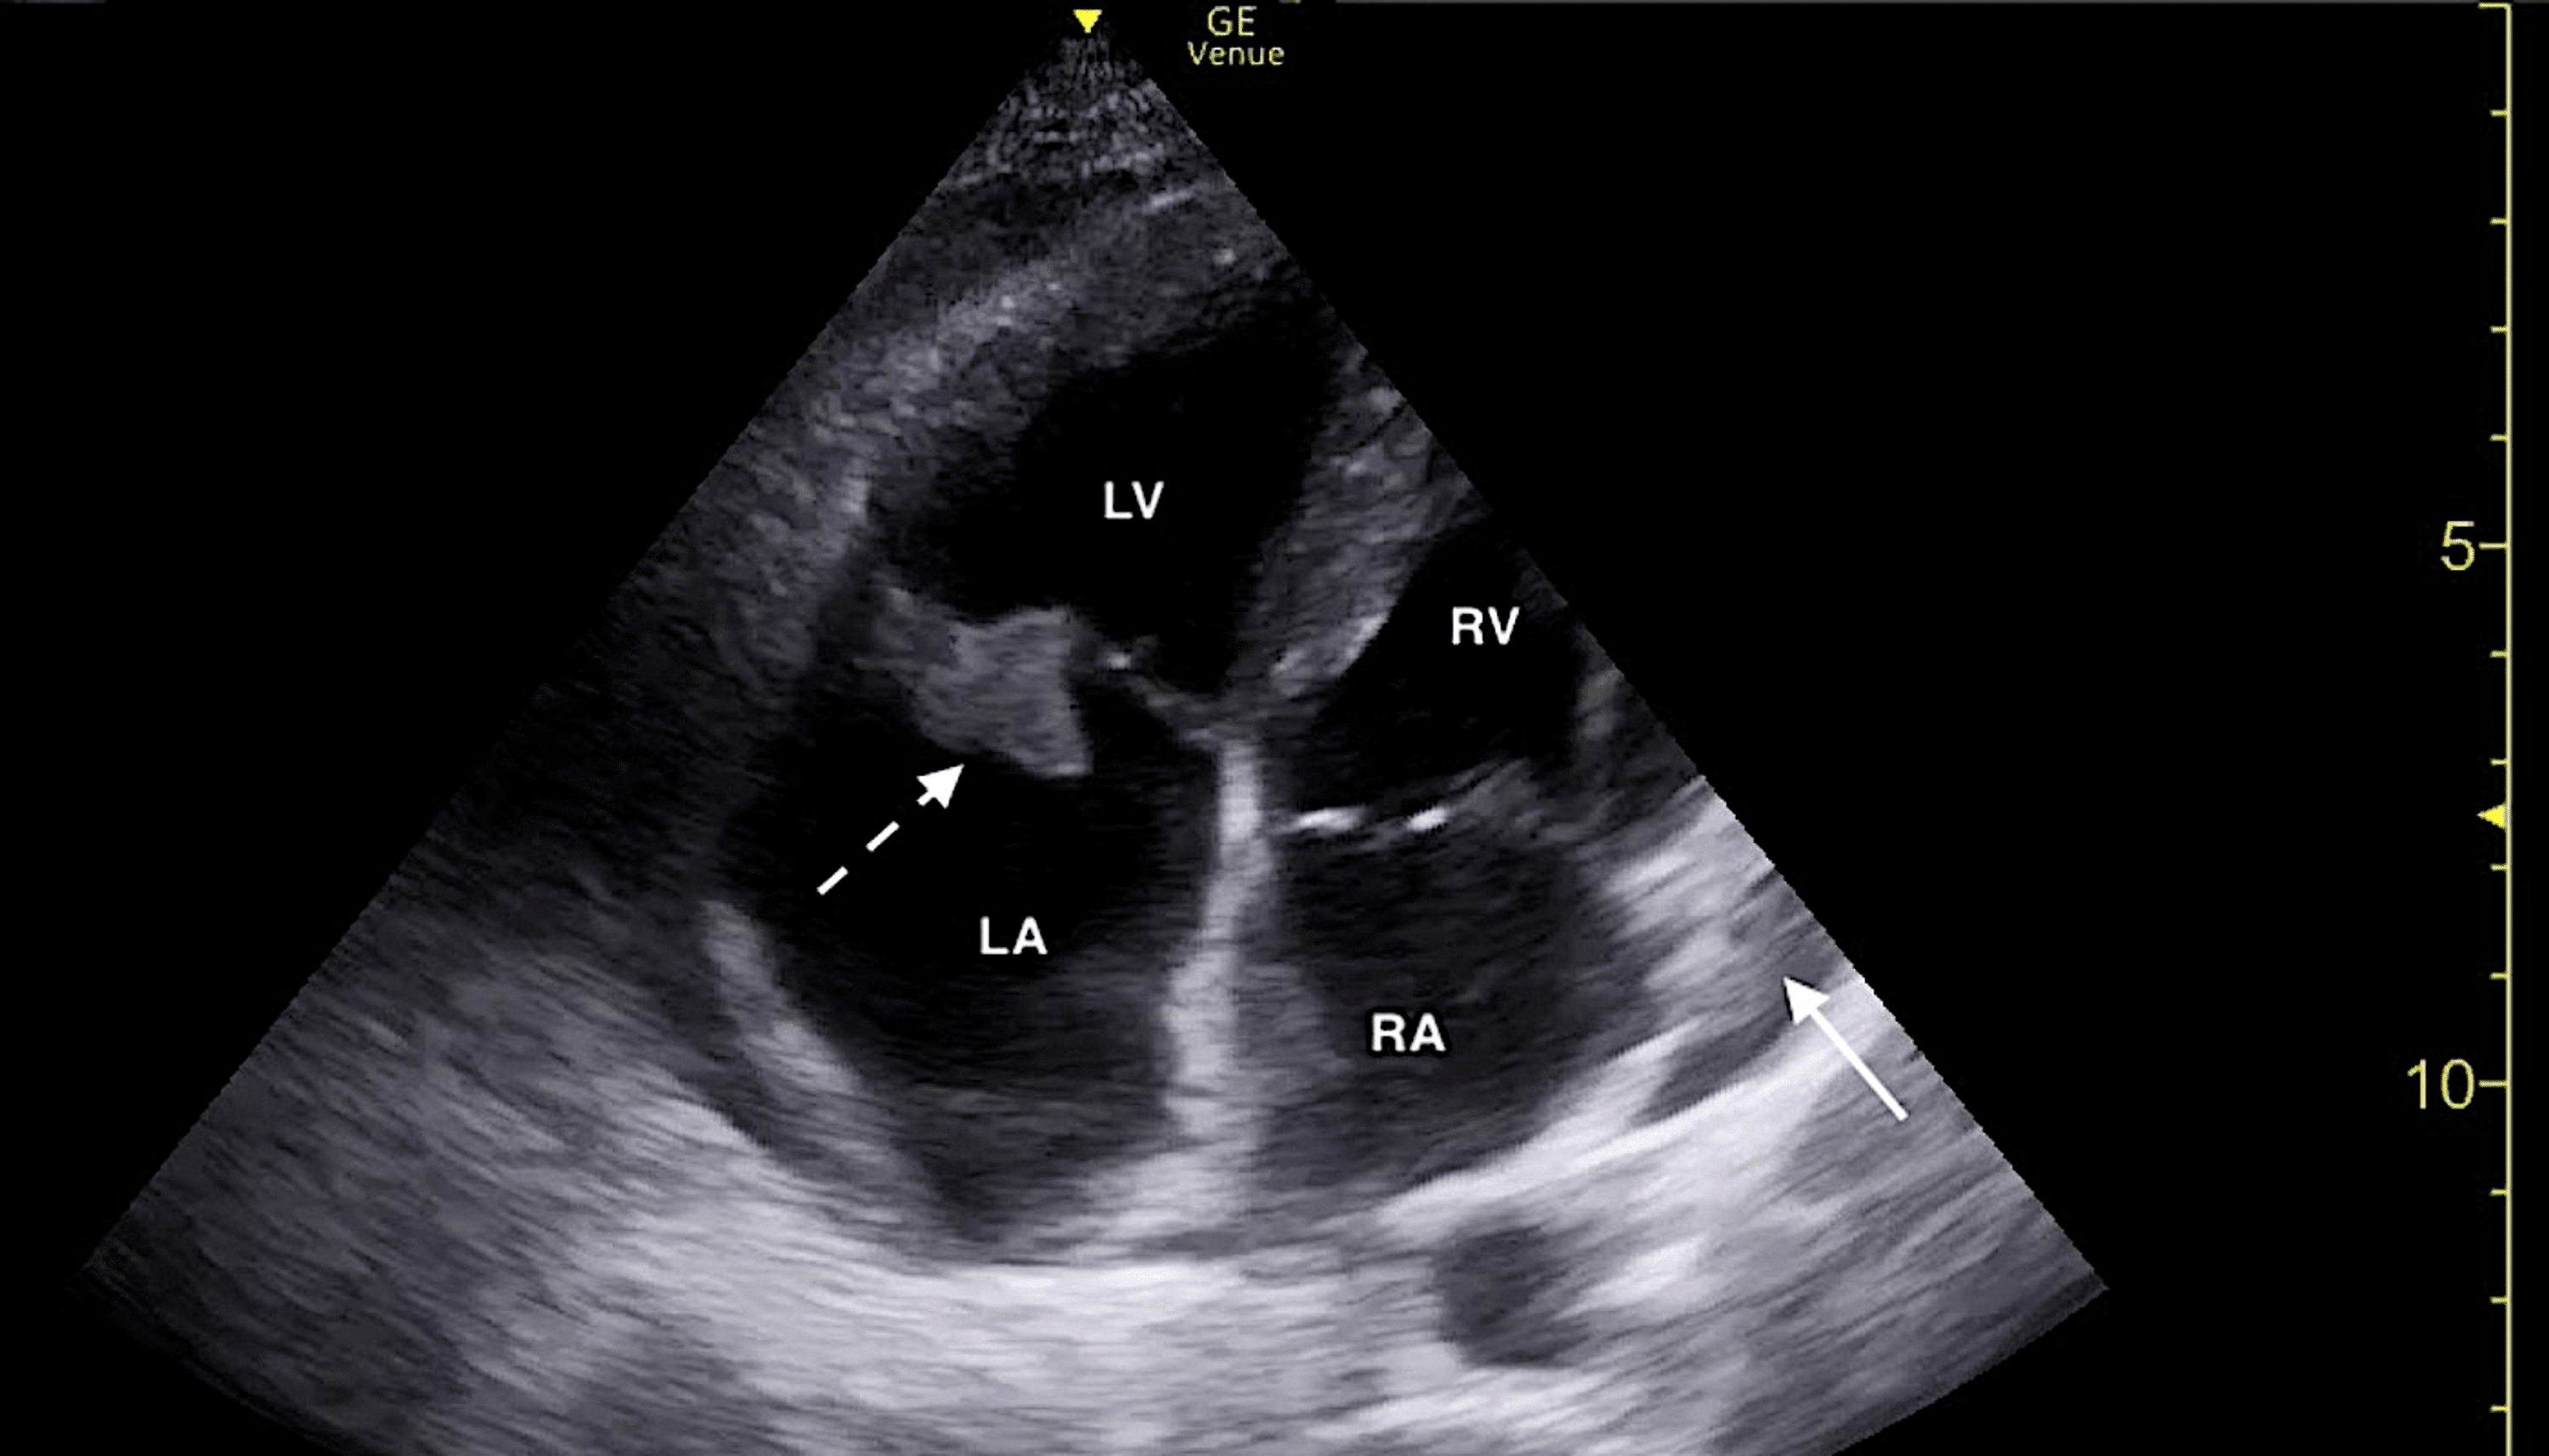

From www.emra.org

Differentiating Acute Versus Chronic Right Heart Failure with Bedside How To Do A Bedside Echo Bedside ultrasound should be used to answer specific questions in real time. Bedside echo is becoming an integral part of intensive care medicine, offering real time haemodynamic evaluation. This video is brought to you by the stanford medicine 25 to teach you how to use bedside point of care ultrasound. Bedside echo is becoming an integral part of intensive care. How To Do A Bedside Echo.